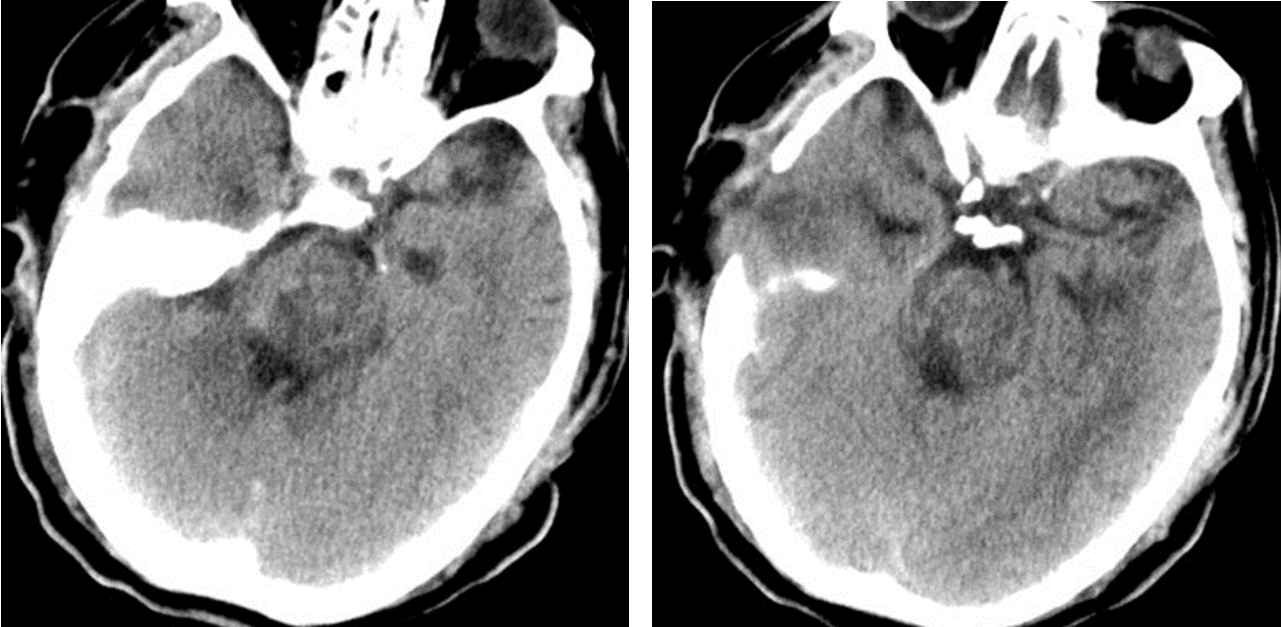

在手術室、麻醉科的積極配合下,整個手術團隊分工有序、緊密配合,采用顳下入路,切開小腦幕,暴露并保護滑車神經、三叉神經、大腦后動脈,應用顯微鏡在橋腦三叉神經上區域通過4毫米的通道,清除腦干內10余毫升出血,并對原發出血部位妥善止血。經過3個多小時的精細操作,在確保最小腦損傷的情況下清除血腫,術中各項監測指標平穩,術后復查頭顱CT顯示血腫清除滿意。術后經過重癥監護室積極治療,患者平穩渡過中樞性高熱、嚴重肺部感染、營養低下等并發癥期,各項生命體征逐步平穩,對外界刺激有適當反應,術后13天轉入普通病房繼續康復促醒治療。

術后患者顱腦CT: